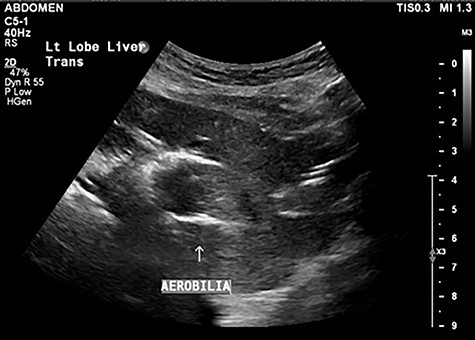

A 90-year-old female presented to the Emergency Department with right upper quadrant pain associated with nausea and persistent vomiting. She had been admitted seven months prior with acute necrotic cholecystitis, but given her advanced age, frailty, medical comorbidities and wishes to avoid surgery, she was managed with intravenous antibiotics and percutaneous cholecystostomy, which was removed eight weeks later. The patient was haemodynamically stable on presentation, but on examination had percussion tenderness in the right upper quadrant. Both abdominal X-ray and ultrasound demonstrated pneumobilia (Figs 1 and 2). A computed tomography (CT) of the abdomen showed a cholecystoduodenal fistula with a 60 × 30-mm gallstone in the third part of the duodenum causing gastric outlet obstruction (GOO), consistent with Bouveret syndrome (Fig. 3).